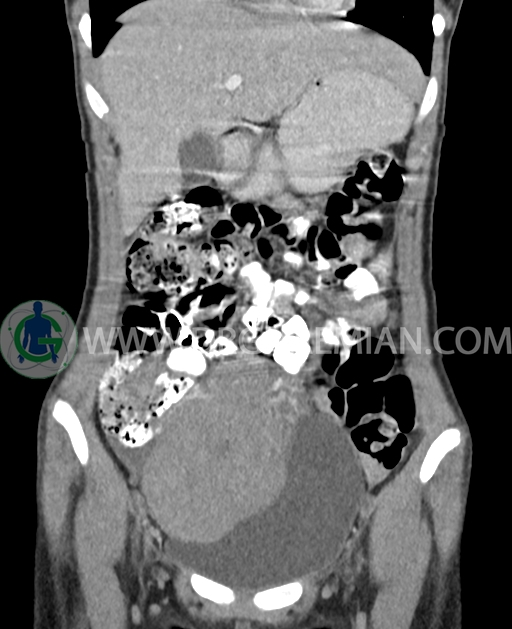

سی تی اسکن شکم و لگن از تشعشعات برای ایجاد تصاویر عرضی مقطعی از نایحه شکم و بین استخوان های لگن استفاده می کند. در این کیس تومور سلول زایا به ابعاد mm 125 x 112 x 80 دیده می شود.

در سی تی اسکن اسپیرال شکم و لگن با کنتراست خوراکی و وریدی (مولتی دیدکتور 16 با مقاطع ظریف و بازسازی های ساژیتال و کرونال) :

توده هیپردنس لوبوله بزرگ به ابعاد 125x112x80mm حاوی نواحی سیستیک داخلی و enhancement قابل توجه پریفرال همراه با آسیت متوسط در فضای شکم و لگن با احتمال بیشتر با منشا از تخمدان راست، درون لگن دیده می شود که در درجه اول مطرح کننده germ cell tumor می باشد .